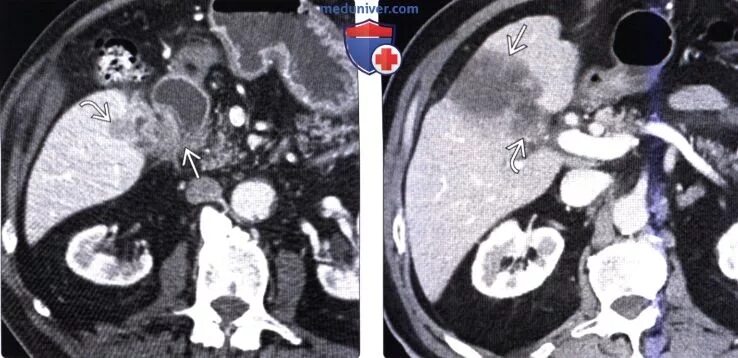

Метастазы в желчном